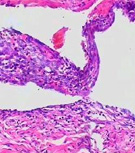

卵巢囊肿

卵巢肿瘤是女性生殖器常见肿瘤,各种年龄均可患病,但以20-50岁较多见。卵巢囊肿有各种不同的性质和形态,以囊性多见,恶性变…更多>>